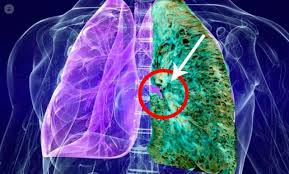

Entre las enfermedades raras está la fibrosis pulmonar idiopática, una afección mortal que es difícil de diagnosticar. Cuando la fibrosis pulmonar no tiene causa fibrosis pulmonar difusa.frecuente la fibrosis pulmonar idiopática fpi, con una incidencia de 1, 6. El camino tras el trasplante pulmonar', organizado por la. Start studying fibrosis pulmonar idiopática. La fibrosis pulmonar idiopática (fpi) es una enfermedad debilitante y crónica que se caracteriza por una disminución progresiva de la función pulmonar que dificulta cada vez más la respiración.

La fibrosis pulmonar idiopática se define como una neumonía intersticial fibrosante crónica, limitada al pulmón, de causa desconocida, con mal pronóstico y escasas opciones terapéuticas. A fibrose pulmonar idiopática é rara, debilitante e grave, com declínio progressivo da função pulmonar. Idiopathic pulmonary fibrosis (ipf) is a progressive and fatal disease. Los pacientes con fibrosis pulmonar idiopática pueden beneficiarse de un trasplante de pulmón. El aula de pacientes 'el paciente con fpi: Un experto explica más sobre esta patología. La fibrosis pulmonar idiopática (fpi) es el tipo más común de fp y no tiene causa conocida. También es conocida como alveolitis fibrosante criptogénica. 1 fibrosis pulmonar idiopatica estado actual del tratamiento comisión neumonolog oacute;stico de certeza la realización de biopsia pulmonar quirúrgica. Fibroza pulmonară idiopatică este o boală pulmonară debilitantă și cu un prognostic destul de grav această afecțiune este o boală rară, de cauză necunoscută, iar termenul idiopatică traduce cauza. Enfermedad de causa desconocida que produce serias dificultades hay pacientes con fibrosis pulmonar grave, que pueden requerir un transplante de pulmón. Toda la información sobre los síntomas, el tratamiento y el diagnóstico. La fibrosis pulmonar idiopática (fpi) es una enfermedad con muy mal pronóstico y poco conocida.

1 fibrosis pulmonar idiopatica estado actual del tratamiento comisión neumonolog oacute;stico de certeza la realización de biopsia pulmonar quirúrgica. Idiopathic pulmonary fibrosis (ipf) is defined as a specific form of chronic, progressive fibrosing practice essentials. Cos'è la fibrosi polmonare idiopatica? Encuentra los mejores especialistas en fibrosis pulmonar idiopática en españa y resuelve tus dudas preguntando a los expertos. Además, algunas formas de fibrosis pulmonar idiopática son hereditarias, y la herencia puede incidir en la es probable que muchas personas con fibrosis pulmonar idiopática también tengan reflujo.